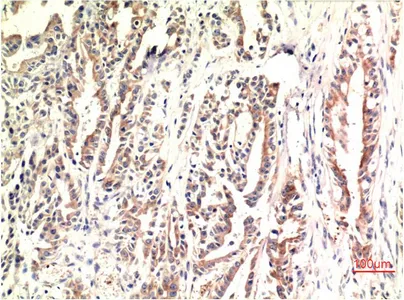

Immunohistochemistry analysis of paraffin-embedded Human Stomach Carcinoma Tissue using CHOP antibody. High-pressure and temperature Sodium Citrate pH 6.0 was used for antigen retrieval.